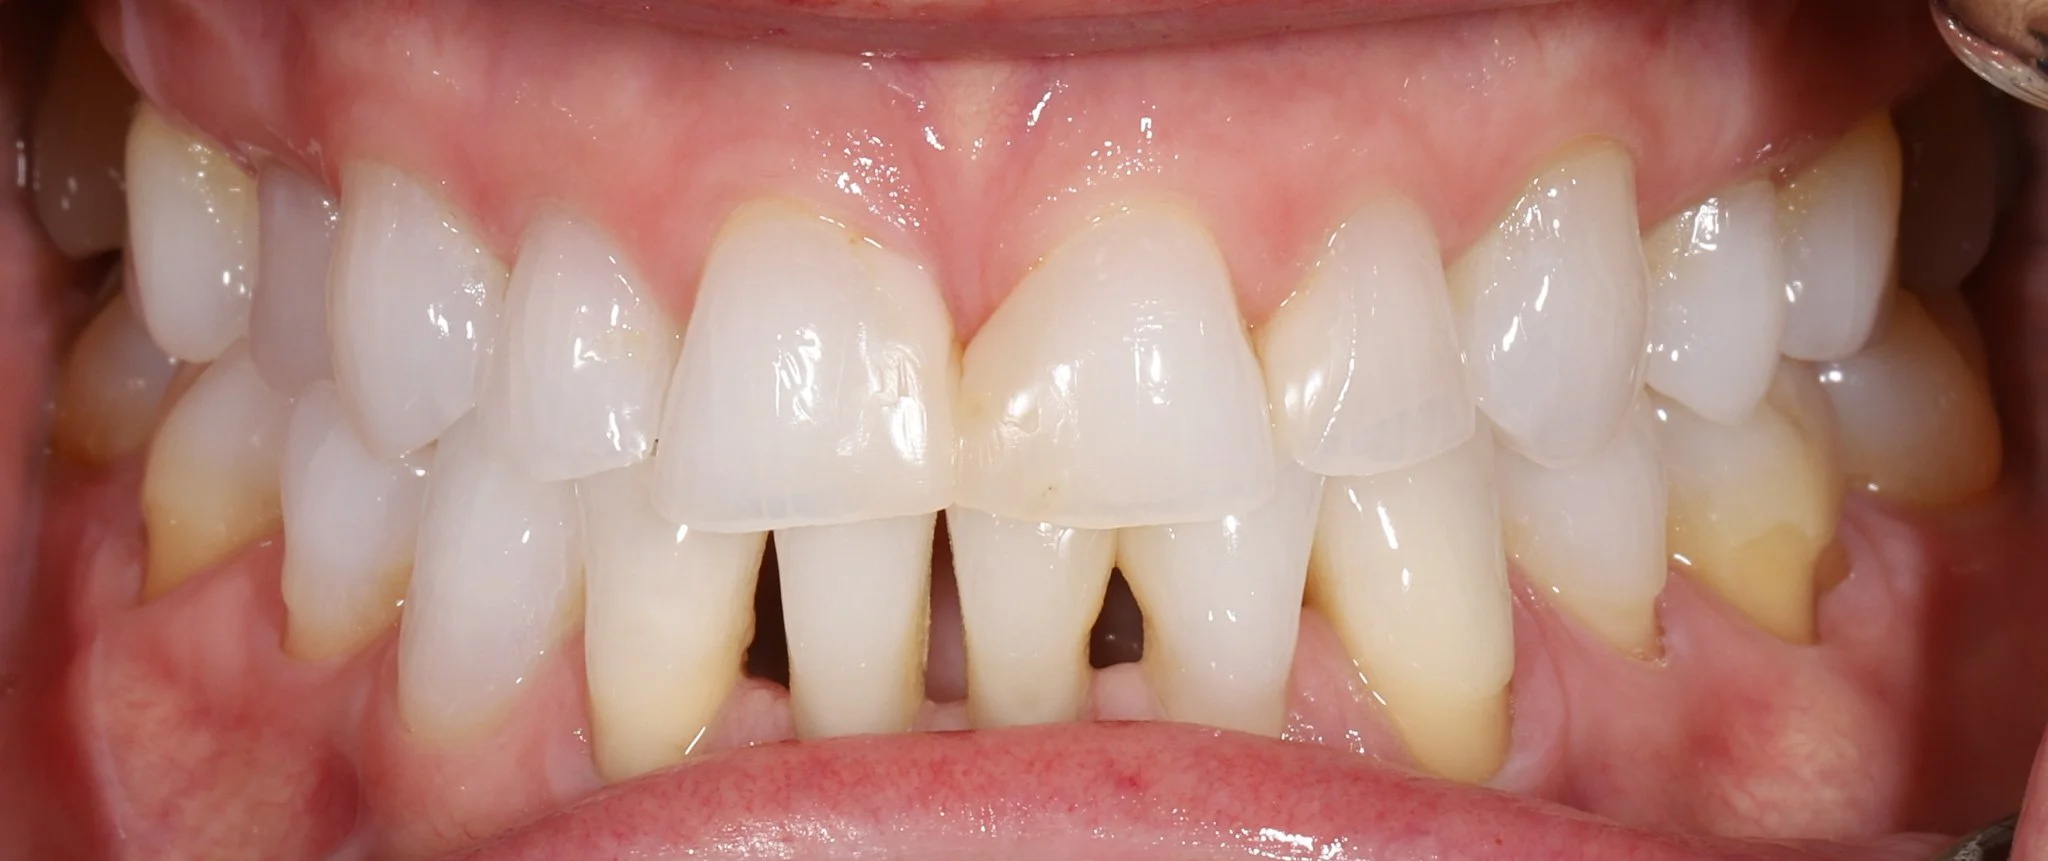

Close-up view of patient's teeth showing wear, acid erosion, misalignment and black triangles.

Before: Acid erosion, wear, bite issues, poor aesethetics

Close-up of a person's upper and lower teeth showing restored smile with proper aesthetics and tooth proportions.

After: Proper aesthetics, gum health, bite reconfigured